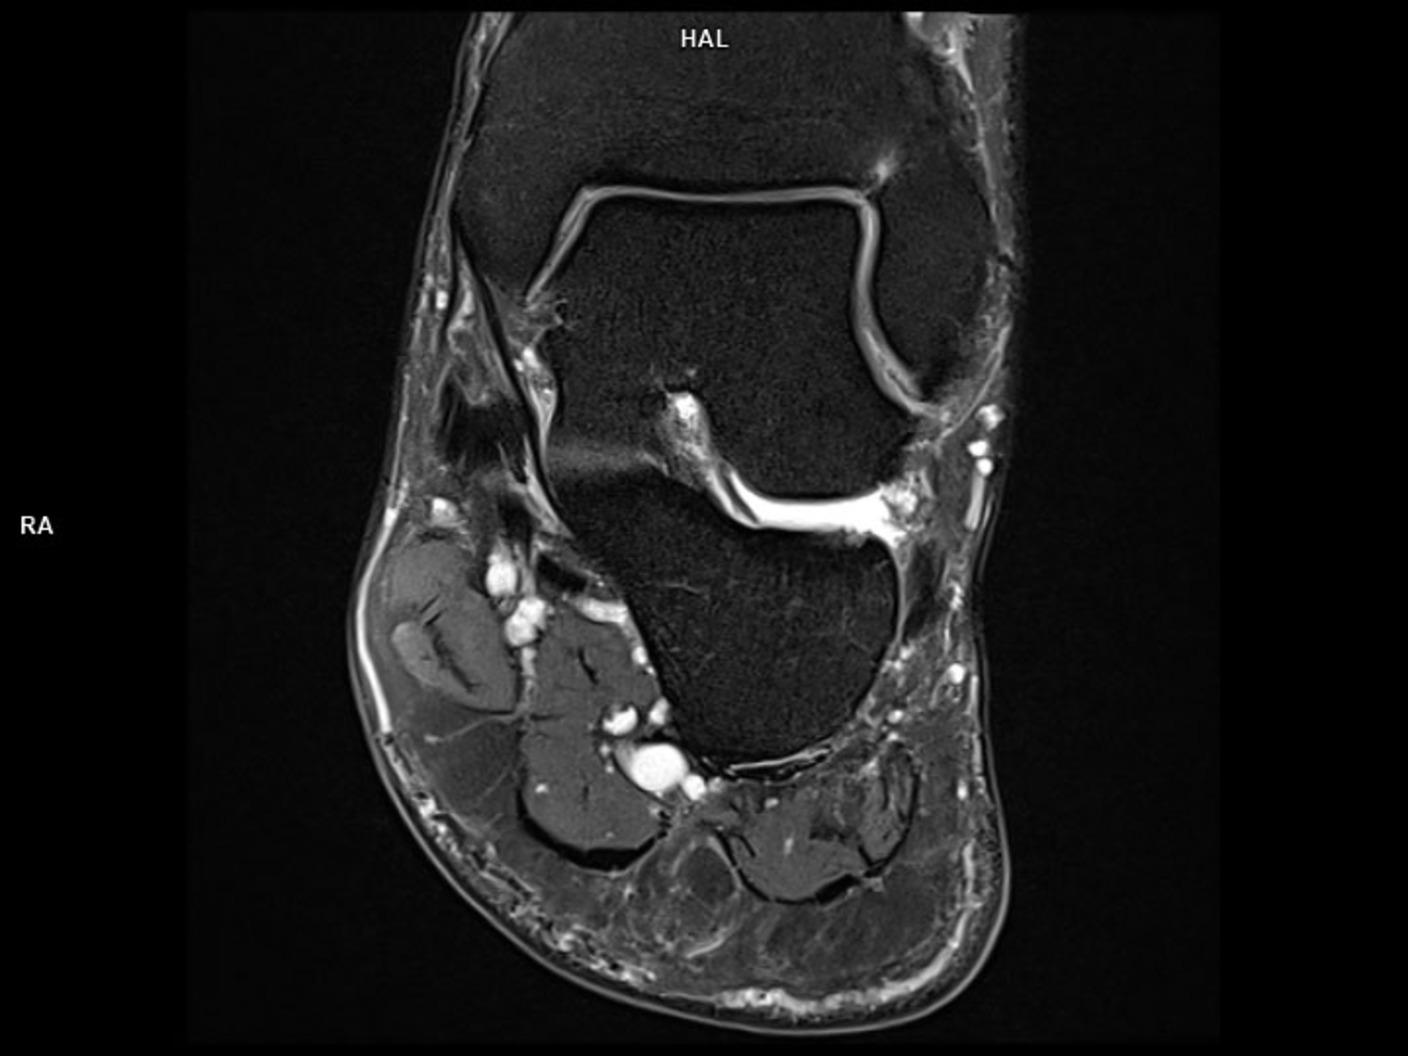

Coronal PD FS-MAGNETOM Lumina

Coil-Foot Ankle 16/Resolution-448/Scan Time 2:15/Aceleration-p2